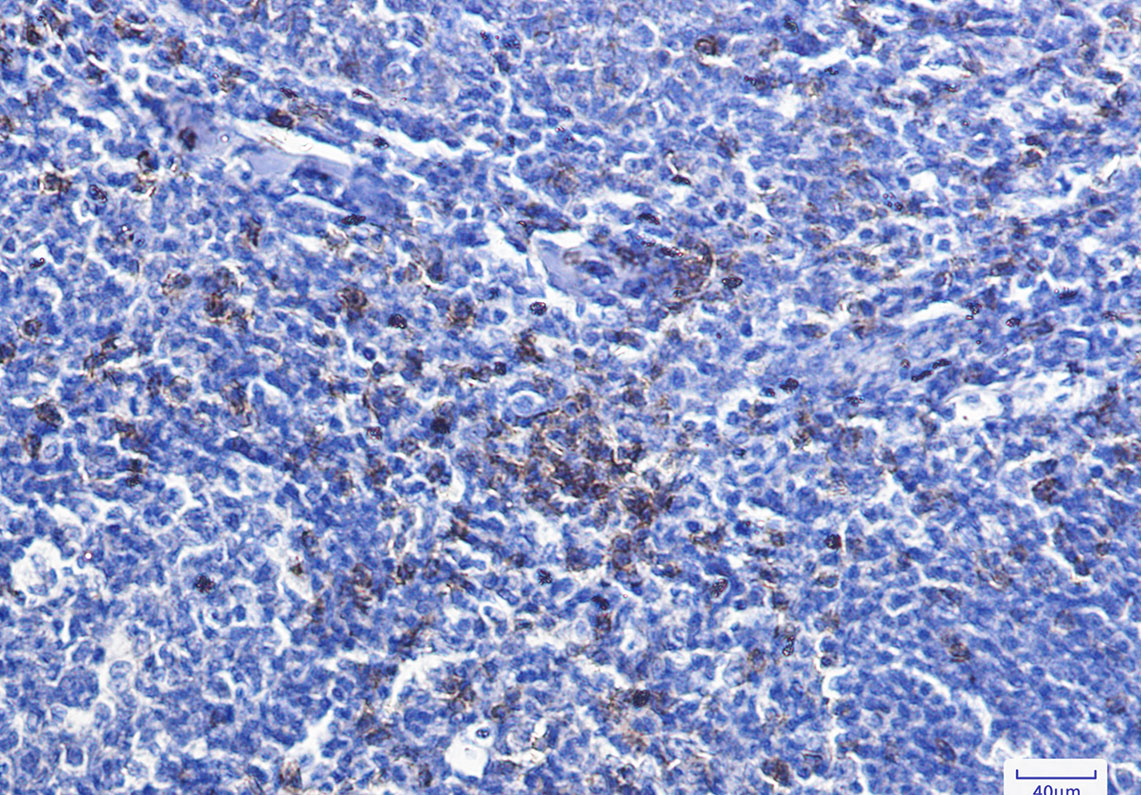

Product Image

- Immunohistochemistry analysis of paraffin-embedded Human tonsil using CD8 antibody. High-pressure and temperature Sodium Citrate pH 6.0 was used for antigen retrieval.